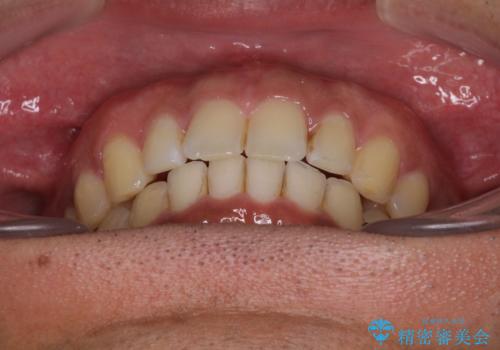

- 上顎前歯の突出感とすきっ歯を気にして来院された患者様です。

奥歯の咬み合わせを見ると、下顎に対して上顎が前方に位置していたため、補助装置により上顎歯列全体を後方に移動させ、その後インビザラインにて歯列全体を整えることとしました。